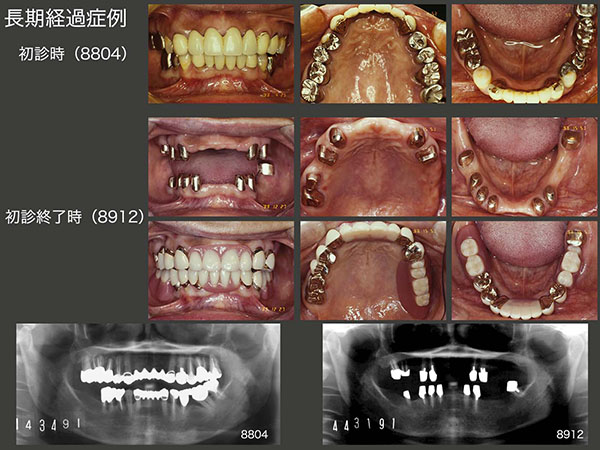

3.長期経過症例

1988年4月初診,43歳女性.左下パノラマX線写真からみてとれるように,全顎的に歯周病に罹患していた.当時の私の技量から保存できる歯を残したうえで,89年12月,上下顎にコーヌス義歯を装着した.

上段のスライドは,コーヌス義歯装着後25年経過した2014年9月の状態.初診終了時上顎は6本,下顎は7本歯が残っていたが,14年には上顎は2本,下顎は3本と,この25年の間に合計8本の歯を失った.しかし,上下顎のコーヌス義歯は25年経過してもなお使用することができた.このように,将来に変化に対応できることがコーヌス義歯の利点の一つである.

しかし,15年9月,上顎左右犬歯のマージン部の2次カリエスが大きくなり,また内外冠の維持力の低下がみられたため,上顎義歯を再製作せざるを得なかった.下顎は,上顎の新義歯に合わせて人工歯を交換したりしているが,昔のままの義歯を使用し続けている.